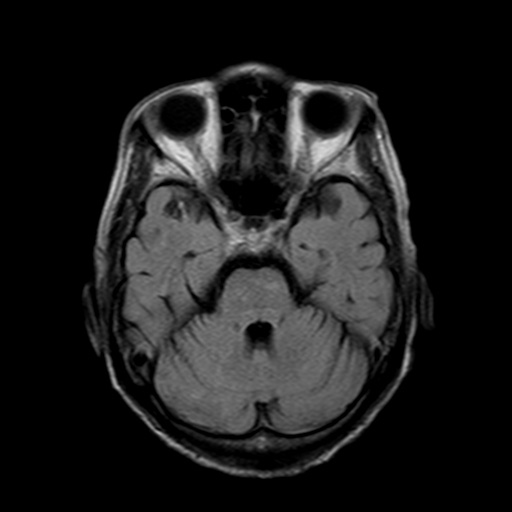

MRIは頭部の断層像で脳腫瘍や梗塞、出血がわかります。MRAは、血管のみ抽出した検査で、くも膜下出血、脳動脈瘤など脳内血管障害の発見に用います。

MRI検査

磁気と電磁波、それに水素原子の動きを利用して、体の断面を撮影する検査で、磁気共鳴画像検査ともいいます。詳細は省きますが、体内の水素が反応して発した信号を捕らえて、コンピューターで解析して画像にしたものです。

MRIではCT検査と同様、腫瘍の大きさや形、数などがわかります。また、MRAでは脳動脈瘤、脳梗塞、脳動静脈奇形、もやもや病、閉塞性動脈病変などの脳血管障害がわかります。脳ドックでは、くも膜下出血の原因となる脳動脈瘤のスクリーニング検査としてよく用いられています。